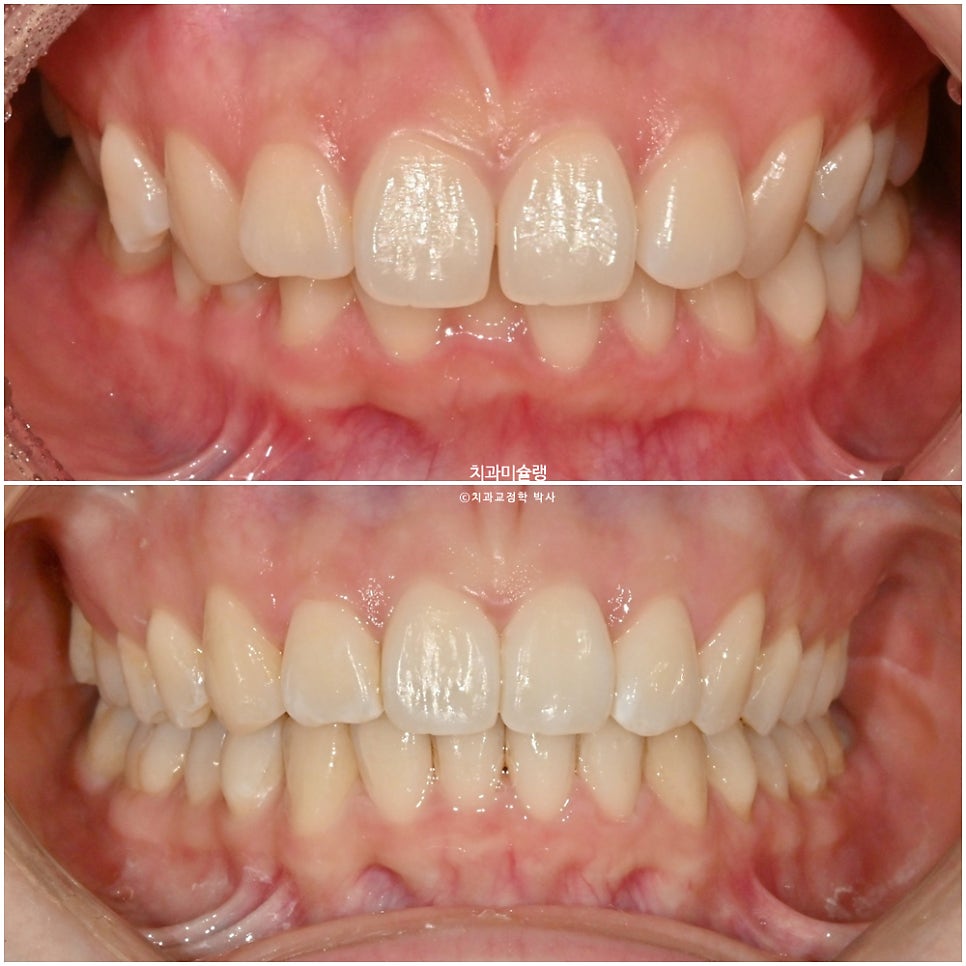

2025년 6월-10월: 첫 번째 장치 세트 적용

25년 6월부터 10월까지, 3개월 반에 걸쳐 14개 장치를 모두 낀 후 모습입니다.

과개교합이, 중심선, 배열의 개선이 보입니다.

어금니 교합은 1급 교합관계를 보이며

여기 저기 붙어있는 금속 고리의 정체는 좀전에 언급한 작은어금니 회전을 위한 부가장치 입니다.

이 부가장치에 고무체인을 걸어놓음으로써 소구치의 회전이 첫세트에서 완료되었는데

최종 치료 결과 – 2026년 3월

어금니 교합은 물샐틈 없는 1급 교합관계를 보입니다.

돌출된 윗니가 뒤로 들어가며 위아래 앞니 사이 간격이 줄었습니다.